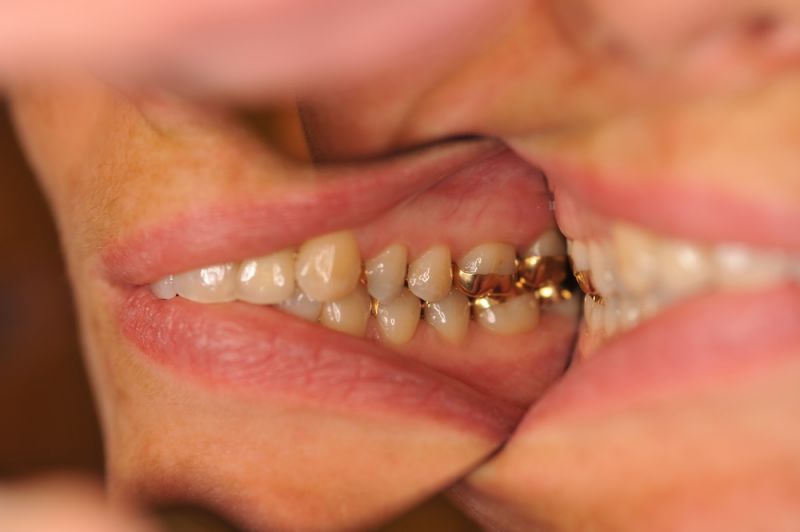

Patientin aus Uelzen zum Recall

11346

Wir würden gerne mal was Neues zeigen, es gibt nur nichts Neues.

Die Arbeit befindet sich seit 23 Jahren unverändert im Munde der Patientin!